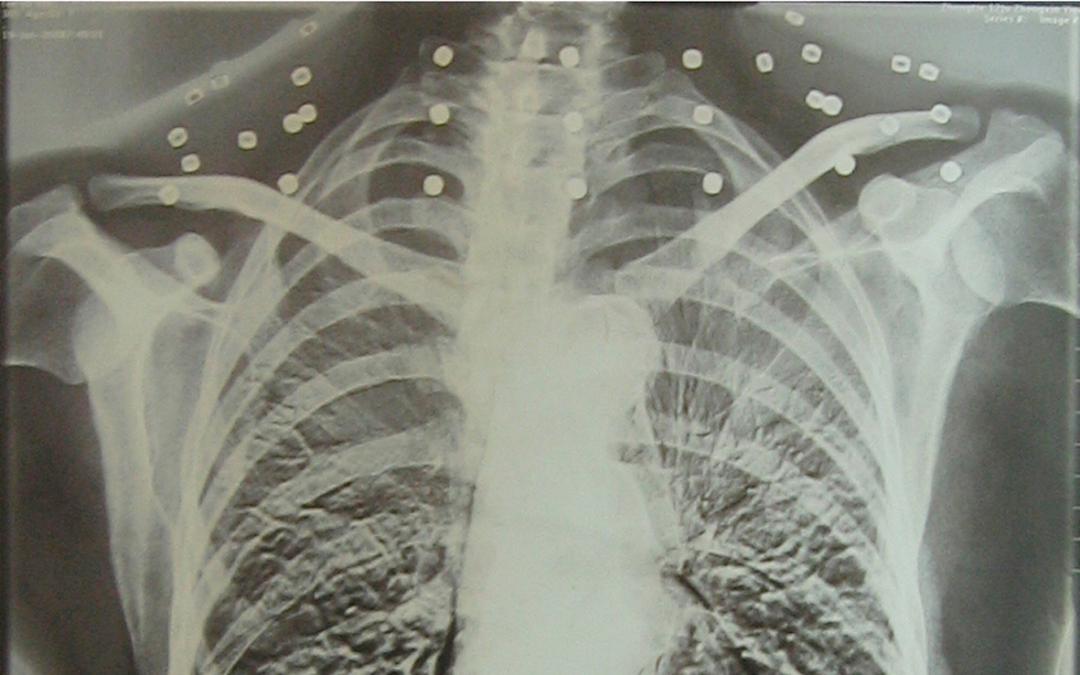

CT影像里所谓的“项链”

原来是炸弹爆炸后

散出的33枚钢珠

“这是菠萝弹的弹珠,共有33颗

已经镶嵌在身体里”

吴以先指着CT胶片上的白点

讲述着60年前

那场惊心动魄的战斗

那些嵌入颈部的弹珠

仅差几毫米就会击穿他的颈部动脉

弹珠一直留在吴以先体内